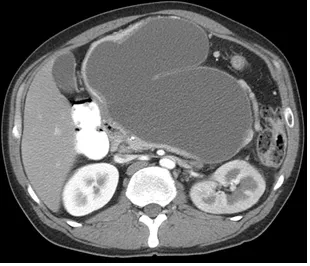

42세 여성이 10일 전부터 지속적인 복통과 38.5도의 발열을 호소하며 내원하였다. 환자는 2주 전에 심한 음주 후 급성 췌장염 진단을 받고 입원 치료를 받았었다. 아래는 복부 초음파 및 복부 CT 결과이다. 가장 적절한 치료 방법은 무엇인가?

[복부 초음파]

[복부 CT]

US, CT: 췌장 부위 경계가 명확한 cyst

Imp: 췌장 가성낭종 (pancreatic pseudocyst)

DDx: 구역성 췌장괴사(walled off necrosis, WON)

• 2주 전 급성 췌장염을 앓은 환자의 US, CT 상 췌장 부위 경계가 명확한 cyst가 관찰되므로 가성 낭종으로 진단 가능하다.

• WON은 경계가 불명확한 피막, heterogenous fluid, 낭종 내부 공기방울이 관찰되어 가성 낭종과 영상 소견 상 차이가 있다.